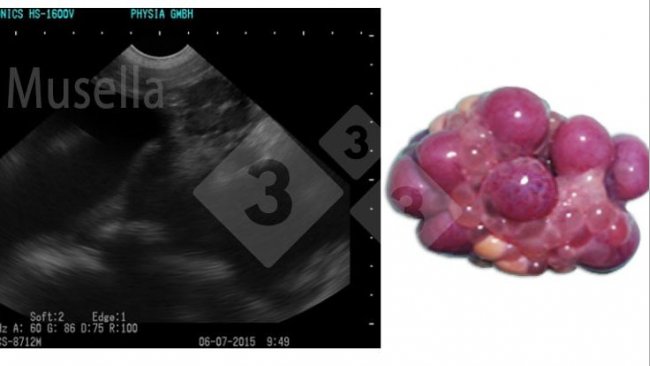

Per quanto riguarda le nuove tecniche con ecografi ad alta definizione, che sono in grado di identificare lo stadio del ciclo della scrofa (l'inseminazione può essere effettuata poco prima o sull'ovulazione), scientificamente sono metodi di grande valore, ma con un'importante esigenza di qualificazione della persona che lo esegue e un'elevata disponibilità del personale, poiché il monitoraggio della crescita follicolare, e quindi del momento del ciclo estrale, richiede ogni giorno più osservazioni, il che rende difficile la loro implementazione a livello aziendale.